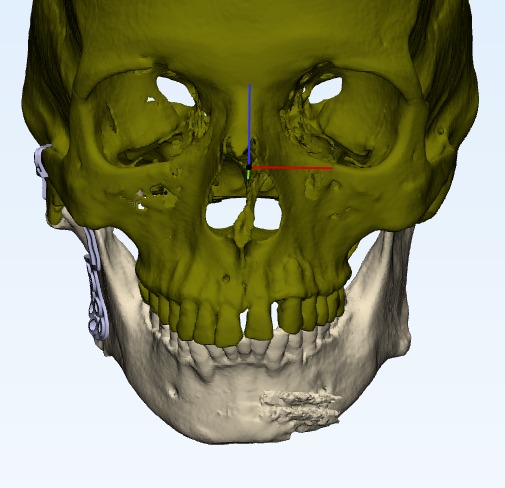

Tmj anklosys leading to deficient mandible and deficient chin corrected by TMJ Surgery followed by Orthognathic surgery